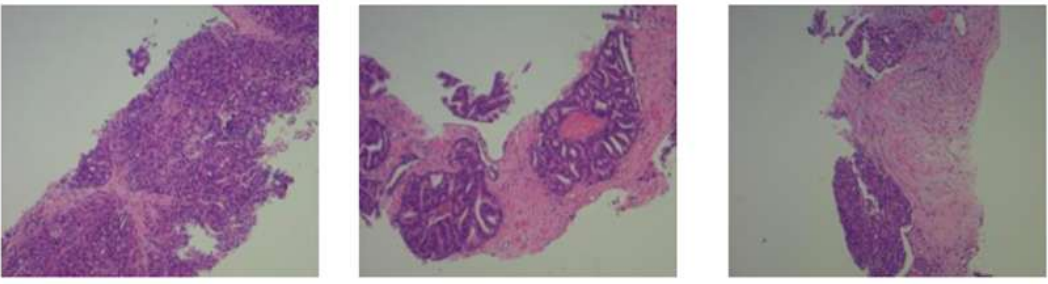

前列腺穿刺活检:前列腺腺泡型腺癌,Gleason4+4=8分,分组4/5,癌占穿刺组织的50%,未见神经侵犯。

图3 2024年11月29日前列腺穿刺病理